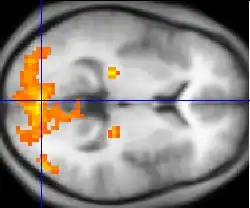

ПЭТ, фМРТ, fNIRS и fUS могут измерять локализованные изменения мозгового кровотока, связанные с нервной активностью. Эти изменения называются активациями. Области мозга, которые активируются, когда субъект выполняет определённую задачу, могут играть определённую роль в вычислительной нейробиологии, которая влияет на поведение. Например, широко распространенная активация затылочной доли обычно наблюдается в задачах, которые включают в себя зрительную систему (по сравнению с задачами, которые этого не делают). Эта часть мозга получает сигналы от сетчатки и играет определённую роль в зрении человека.

Традиционные «исследования активации» сосредоточены на определении распределенных паттернов мозговой активности, связанных с конкретными задачами. Однако ученые могут более глубоко понять функции мозга, изучая взаимодействие различных областей мозга, поскольку большая часть нейронной обработки выполняется интегрированной сетью из нескольких областей мозга. Активная область исследований в области нейровизуализации включает изучение функциональной связи пространственно удаленных областей мозга. Анализ функциональных связей позволяет охарактеризовать межрегиональные нейронные взаимодействия во время выполнения конкретных когнитивных или двигательных задач или просто в результате спонтанной активности во время отдыха. ФМРТ и ПЭТ позволяют создавать карты функциональной связанности различных пространственных распределений временно коррелированных областей мозга, называемых функциональными сетями. Несколько исследований с использованием методов нейровизуализации также установили, что задние зрительные области у слепых людей могут быть активны во время выполнения невизуальных задач, таких как чтение по Брайлю, восстановление памяти и слуховая локализация, а также другие слуховые функции[5].

Исследования функциональной нейровизуализации должны быть тщательно разработаны и тщательно интерпретированы. Статистический анализ (часто с использованием метода, называемого статистическим параметрическим отображением) нередко необходим для того, чтобы различные источники активации в мозге можно было отличить друг от друга. Это может быть особенно сложно при рассмотрении процессов, которые трудно концептуализировать или с которыми не связана легко определяемая задача (например, вера и сознание).